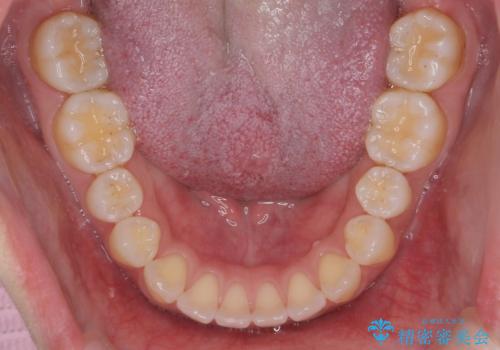

受け口、すきっ歯を インビザラインで モニター治療

- 前歯のすき間と受け口を気にして来院。

マウスピースでしっかり閉じています。

下の前歯を後方に移動するため、ゴムを上下のマウスピースにかけてもらいました。